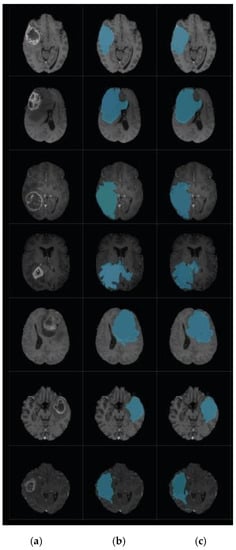

3.3. Level Set Segmentation

| 1: Insert initial contour points using two-step DA clustering output (ROI indexes). 2: Construct a signed distance function. 3: Calculate feature image using Gaussian filter and gradient. 4: Obtain the curve’s narrow band. 5: Obtain curvature and use gradient descent to minimize energy. 6: Evolve the curve. 7: Repeat step number two and stop after obtaining the segmented region. |